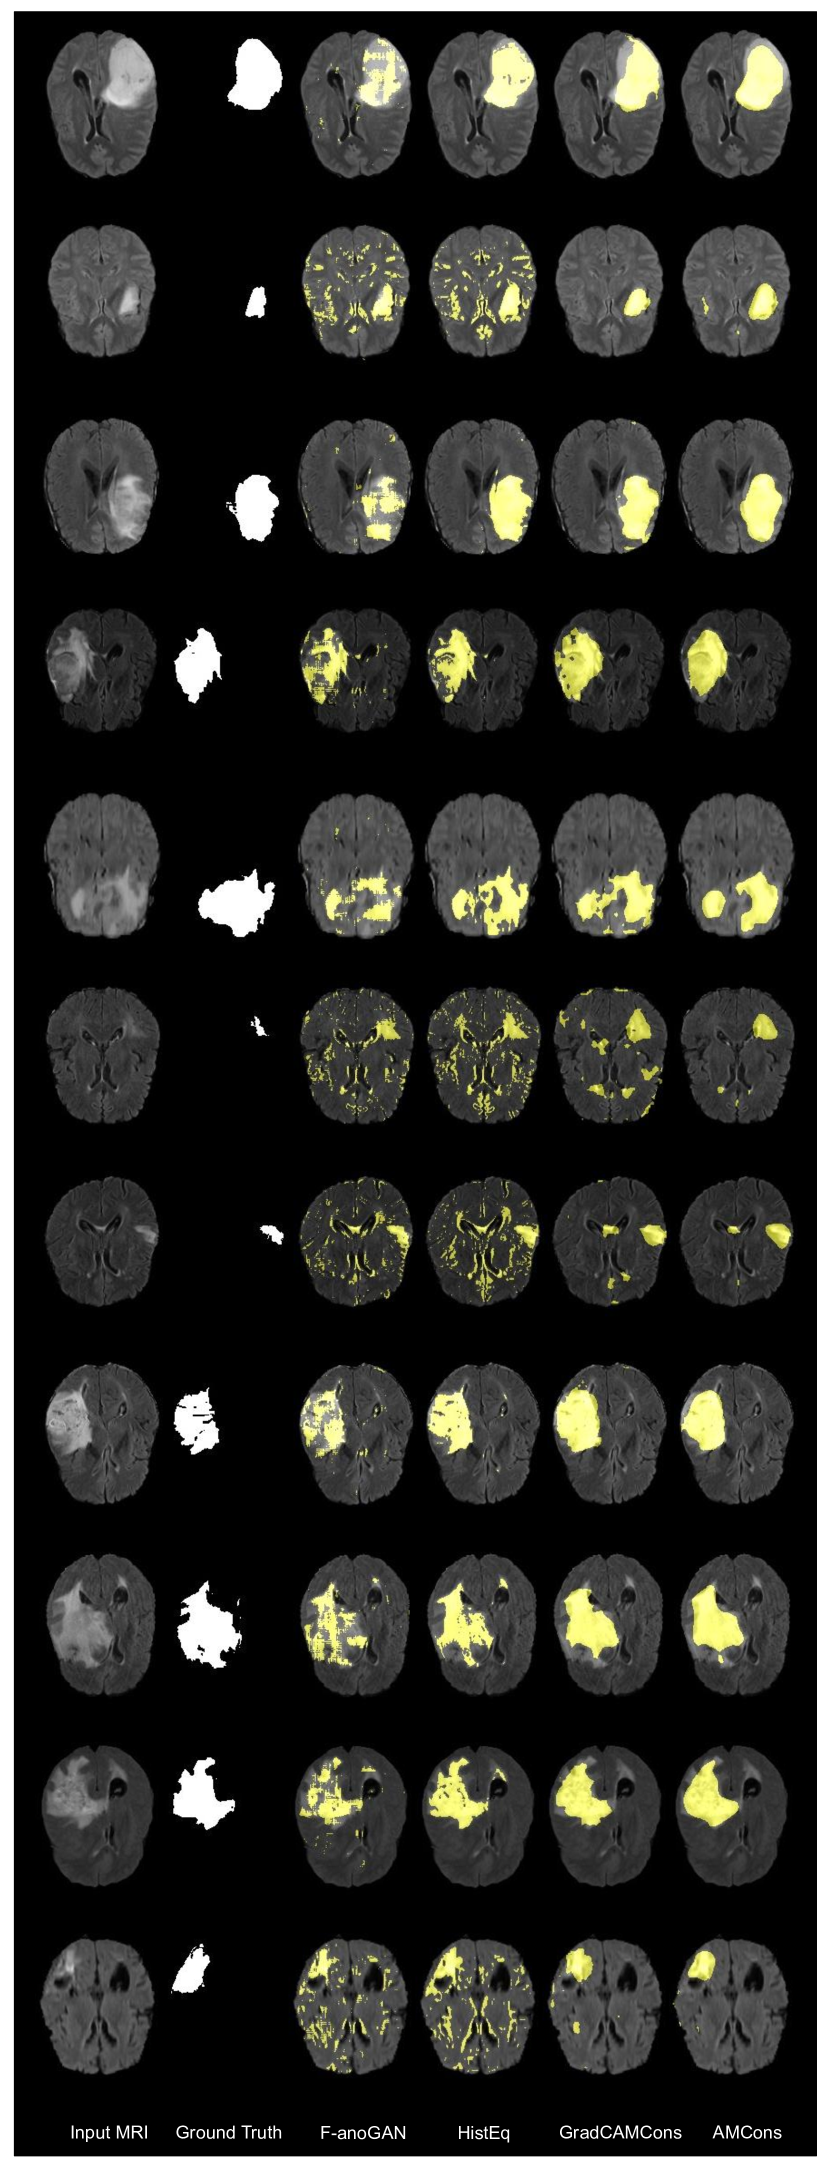

5.4 Qualitative evaluation

Visual results of the proposed and existing methods for both datasets are depicted in Figure 8. We can observe that our approach identifies as anomalous more complete regions of the lesions, whereas existing methods are prone to produce a significant amount of false positives (first, third and seventh rows) and fail to discover many abnormal pixels (third row). These visual results are in line with the quantitative validation performed in previous sections. However, there is a known problem about segmenting only hyperintense regions in the state-of-the-art methods of unsupervised anomaly localization of brain lesions ([31]). Although the proposed method still suffers from this limitation (fourth row, red arrow), the positive results regarding true negative segmentation obtained in some normal, hyperintense tissue (second row, green arrow) suggest an improvement in relation to this problem.

5 Additional qualitative visualizations